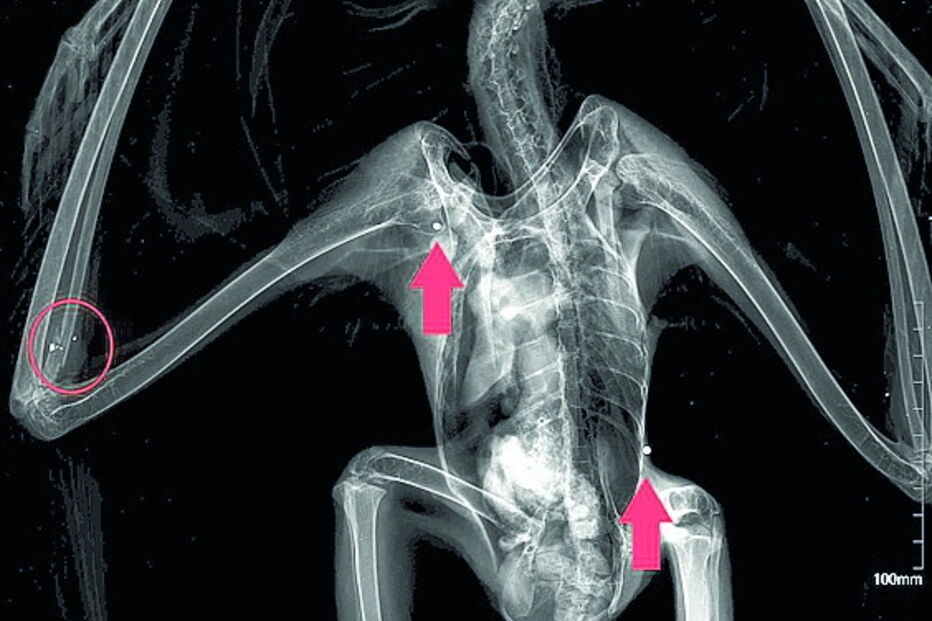

Ave de rapina tinha três projéteis alojados no corpo. Durante a cirurgia só foi possível retirar um.

A ave de rapina deu entrada no RIAS no passado domingo, tendo, durante o exame físico, sido detetada uma fratura no rádio direito. "Suspeitando-se de tiro, a equipa veterinária decidiu realizar um exame radiológico, em que se confirmaram as suspeitas. Foram identificados três projéteis de caçadeira: na cabeça, ombro direito e costado esquerdo, e restos de um quarto projétil no foco da fratura", revelou o centro, que esclareceu ter sido possível "retirar um dos projéteis". Contudo, "os restantes não puderam ser extraídos por questões médicas", referiu.